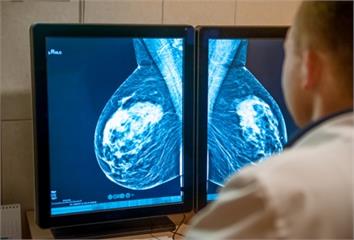

三陰性乳癌 健康 中西醫聯手對抗三陰性乳癌 減輕副作用助患者完成化... 2025.10.30 15:00 陳小姐61歲,於今年2月自行觸摸發現左側乳房有硬塊,經西醫檢查確診為第一期三陰性乳癌,腫瘤大小達13.2 × 11.7 × 15.9毫米。三陰性乳癌雖僅佔所有乳癌約一至兩成,但... 健康 61歲婦人確診三陰性乳癌 中西醫攜手治療帶來希望 2025.10.06 17:06 61歲的陳小姐今年2月自行檢查時,發現左側乳房有硬塊,經檢查確診為第一期「三陰性乳癌」,腫瘤大小達13.2 × 11.7 × 15.9毫米。雖然三陰性乳癌僅佔乳癌總數的一至兩成... 生活 興大研發雙嵌入劑癌症新藥 「三陰性乳癌」曙光 2025.05.06 15:41 乳癌是全球女性最常見的惡性腫瘤之一,在台灣亦高居女性癌症發生率與死亡率之首,其中約15%的三陰性乳癌,因缺乏有效標靶藥物,為臨床上最具挑戰性的乳癌亞型之一,中興大學的研究團隊研發出一款複方新藥,能有效... 健康 面對棘手三陰性乳癌別慌 1藥物能對抗癌細胞、延長... 2023.09.21 16:53 根據國民健康署最新數據顯示,2020年國人新發生癌症人數為12萬1979人,平均每4分19秒就有一人罹癌。因此,如何有意識的防癌,讓癌症盡可能遠離自己的生活,成為了現代人應該具備的生活思維;但若是不幸... 健康 女性國人最常發生「1癌症」 抗體藥物複合體ADC... 2023.07.21 18:30 乳癌一直是國內女性民眾發生率最高的癌症,經過衛生福利部國民健康署多年推行的乳癌篩檢,對於乳癌早期的診斷有相當的助益,進而改善其存活率。但仍有少數女性患者面臨著乳癌的復發而影響其健康。不同型的乳癌 治療... 健康 胸部發出惡臭、流血 乳癌已經第四期了!透過1方延... 2023.06.29 15:48 68歲陳小姐因左側乳房巨大腫瘤穿破胸壁,不僅流血還發出惡臭,來到醫院急診,診斷為蜂窩性組織炎,緊急照會感染科及一般外科王聖麟醫師,遂安排電腦斷層檢查、病理組織切片,發現為第四期「三陰性乳癌」。以抗生素... 健康 乳房「刺刺的」小心最惡性乳癌上身! 醫解析「三陰... 2022.08.12 21:05 三陰性乳癌惡性高、預後差?房仲甜心自摸右乳「刺刺的」,機警就醫,意外發現2.9公分腫瘤合併多顆腋下淋巴結轉移,確診早期高風險性三陰性乳癌,錯愕不已,但她決定微笑以對,聽從醫師建議,陸續完成三階段治療,... 健康 每37分鐘1女性確診!是你嗎? 乳癌「危險因子... 2021.04.22 20:00 歌手朱俐靜罹患乳癌,引起不少歌迷震驚,法務部前部長、兒福聯盟基金會董事長羅瑩雪日前死於乳癌,享壽69歲,更讓人深感惋惜,這也讓最近幾天各大醫院乳房外科門診求診人數明顯增加。乳癌 女性癌症發生率第1位根...